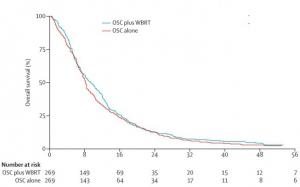

CANCER du POUMON: Pas d'effet de la radiothérapie pour les tumeurs cérébrales secondaires